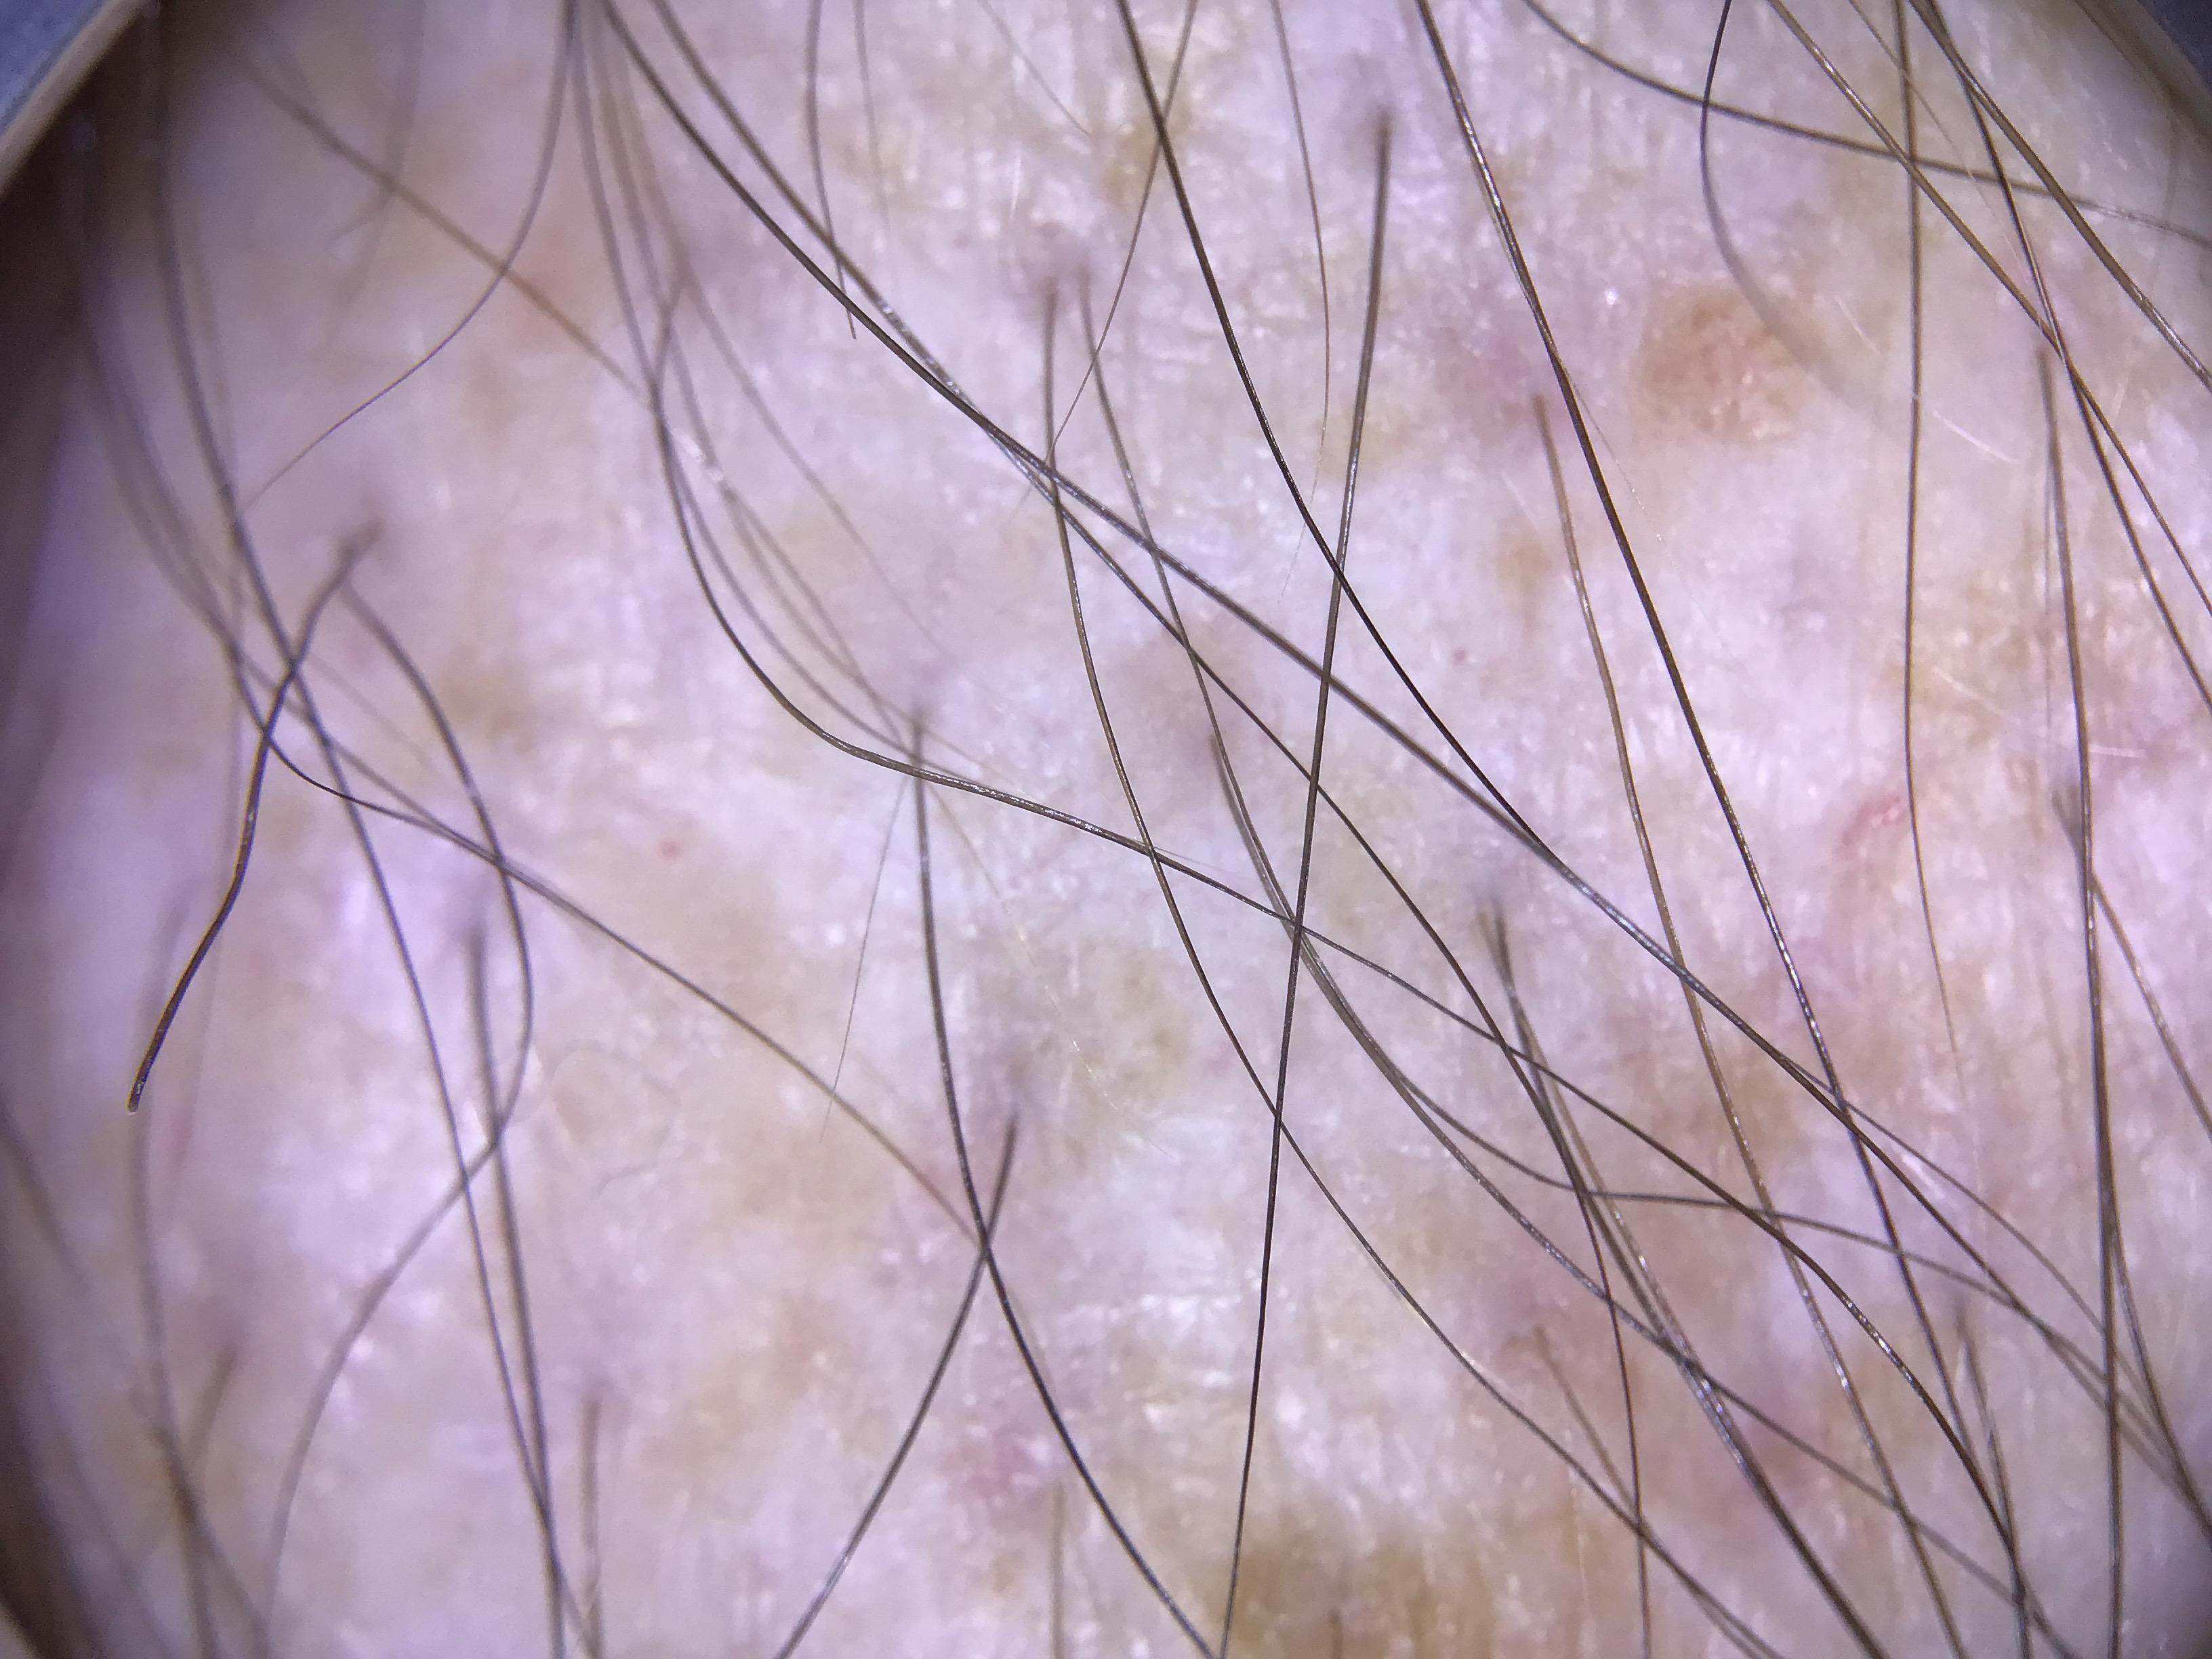

The dataset comprises both patient-level and site-level metadata for skin tone classification using the Fitzpatrick Skin Type scale, Monk Skin Tone scale, Pantone SkinTone Guide, and colorimeter readings (SkinColorCatch, Delfin Technologies). A total of 4,879 dermoscopic images are included. Skin tone assessments were collected across both lesional and non-lesional (normal skin) sites, mapped to standardized anatomic locations. All skin lesions are assumed to be benign, as they were imaged immediately following dermatologic evaluation.